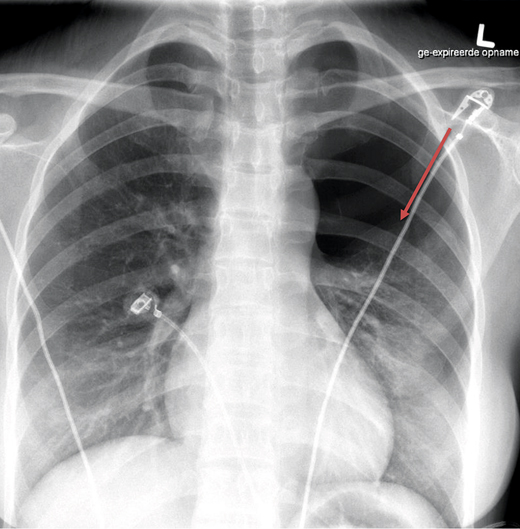

Acupunctuur is relatief veilig, maar kan leiden tot complicaties. Een zeer zeldzame, maar ernstige complicatie is een pneumothorax. Bij thoracale pijnklachten na een acupunctuurbehandeling moet altijd een pneumothorax worden overwogen. Risicofactoren zijn acupunctuur van thorax, schouders en bovenrug, een niet goed uitgevoerde procedure en longemfyseem of longkanker in de voorgeschiedenis.